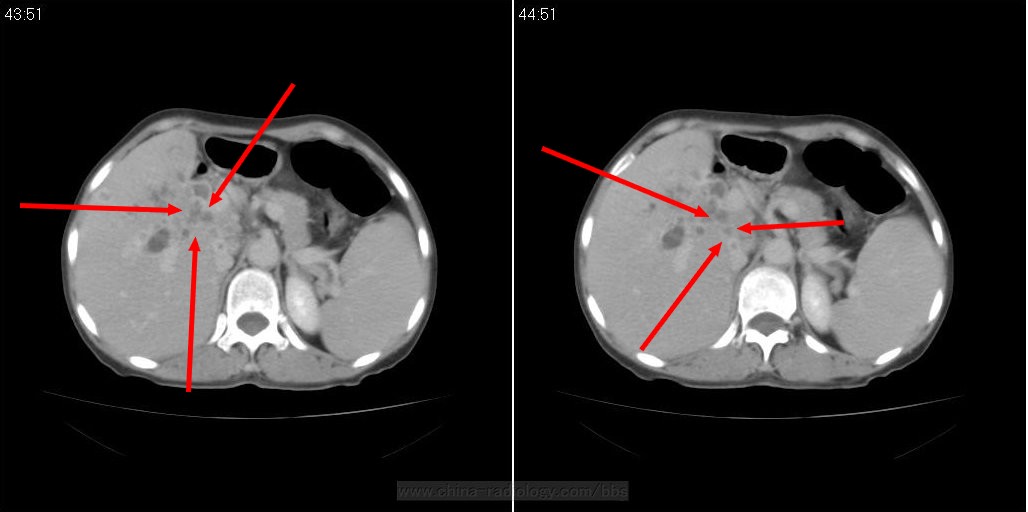

标题: CT21075:难啊,肝门不均匀强化考虑什么呢?

女性,60岁。右侧腹痛。最近厌食、纳差,体质明显消瘦(两个月来体重减少20多斤)。十年前曾经做过胆囊结石手术。但总管扩张,其内可见低密度结石影。

增强图片:

增强图片已经上传,各位老师帮助诊断分析一下

标题: 箭头所指非常奇怪,呈串珠状改变